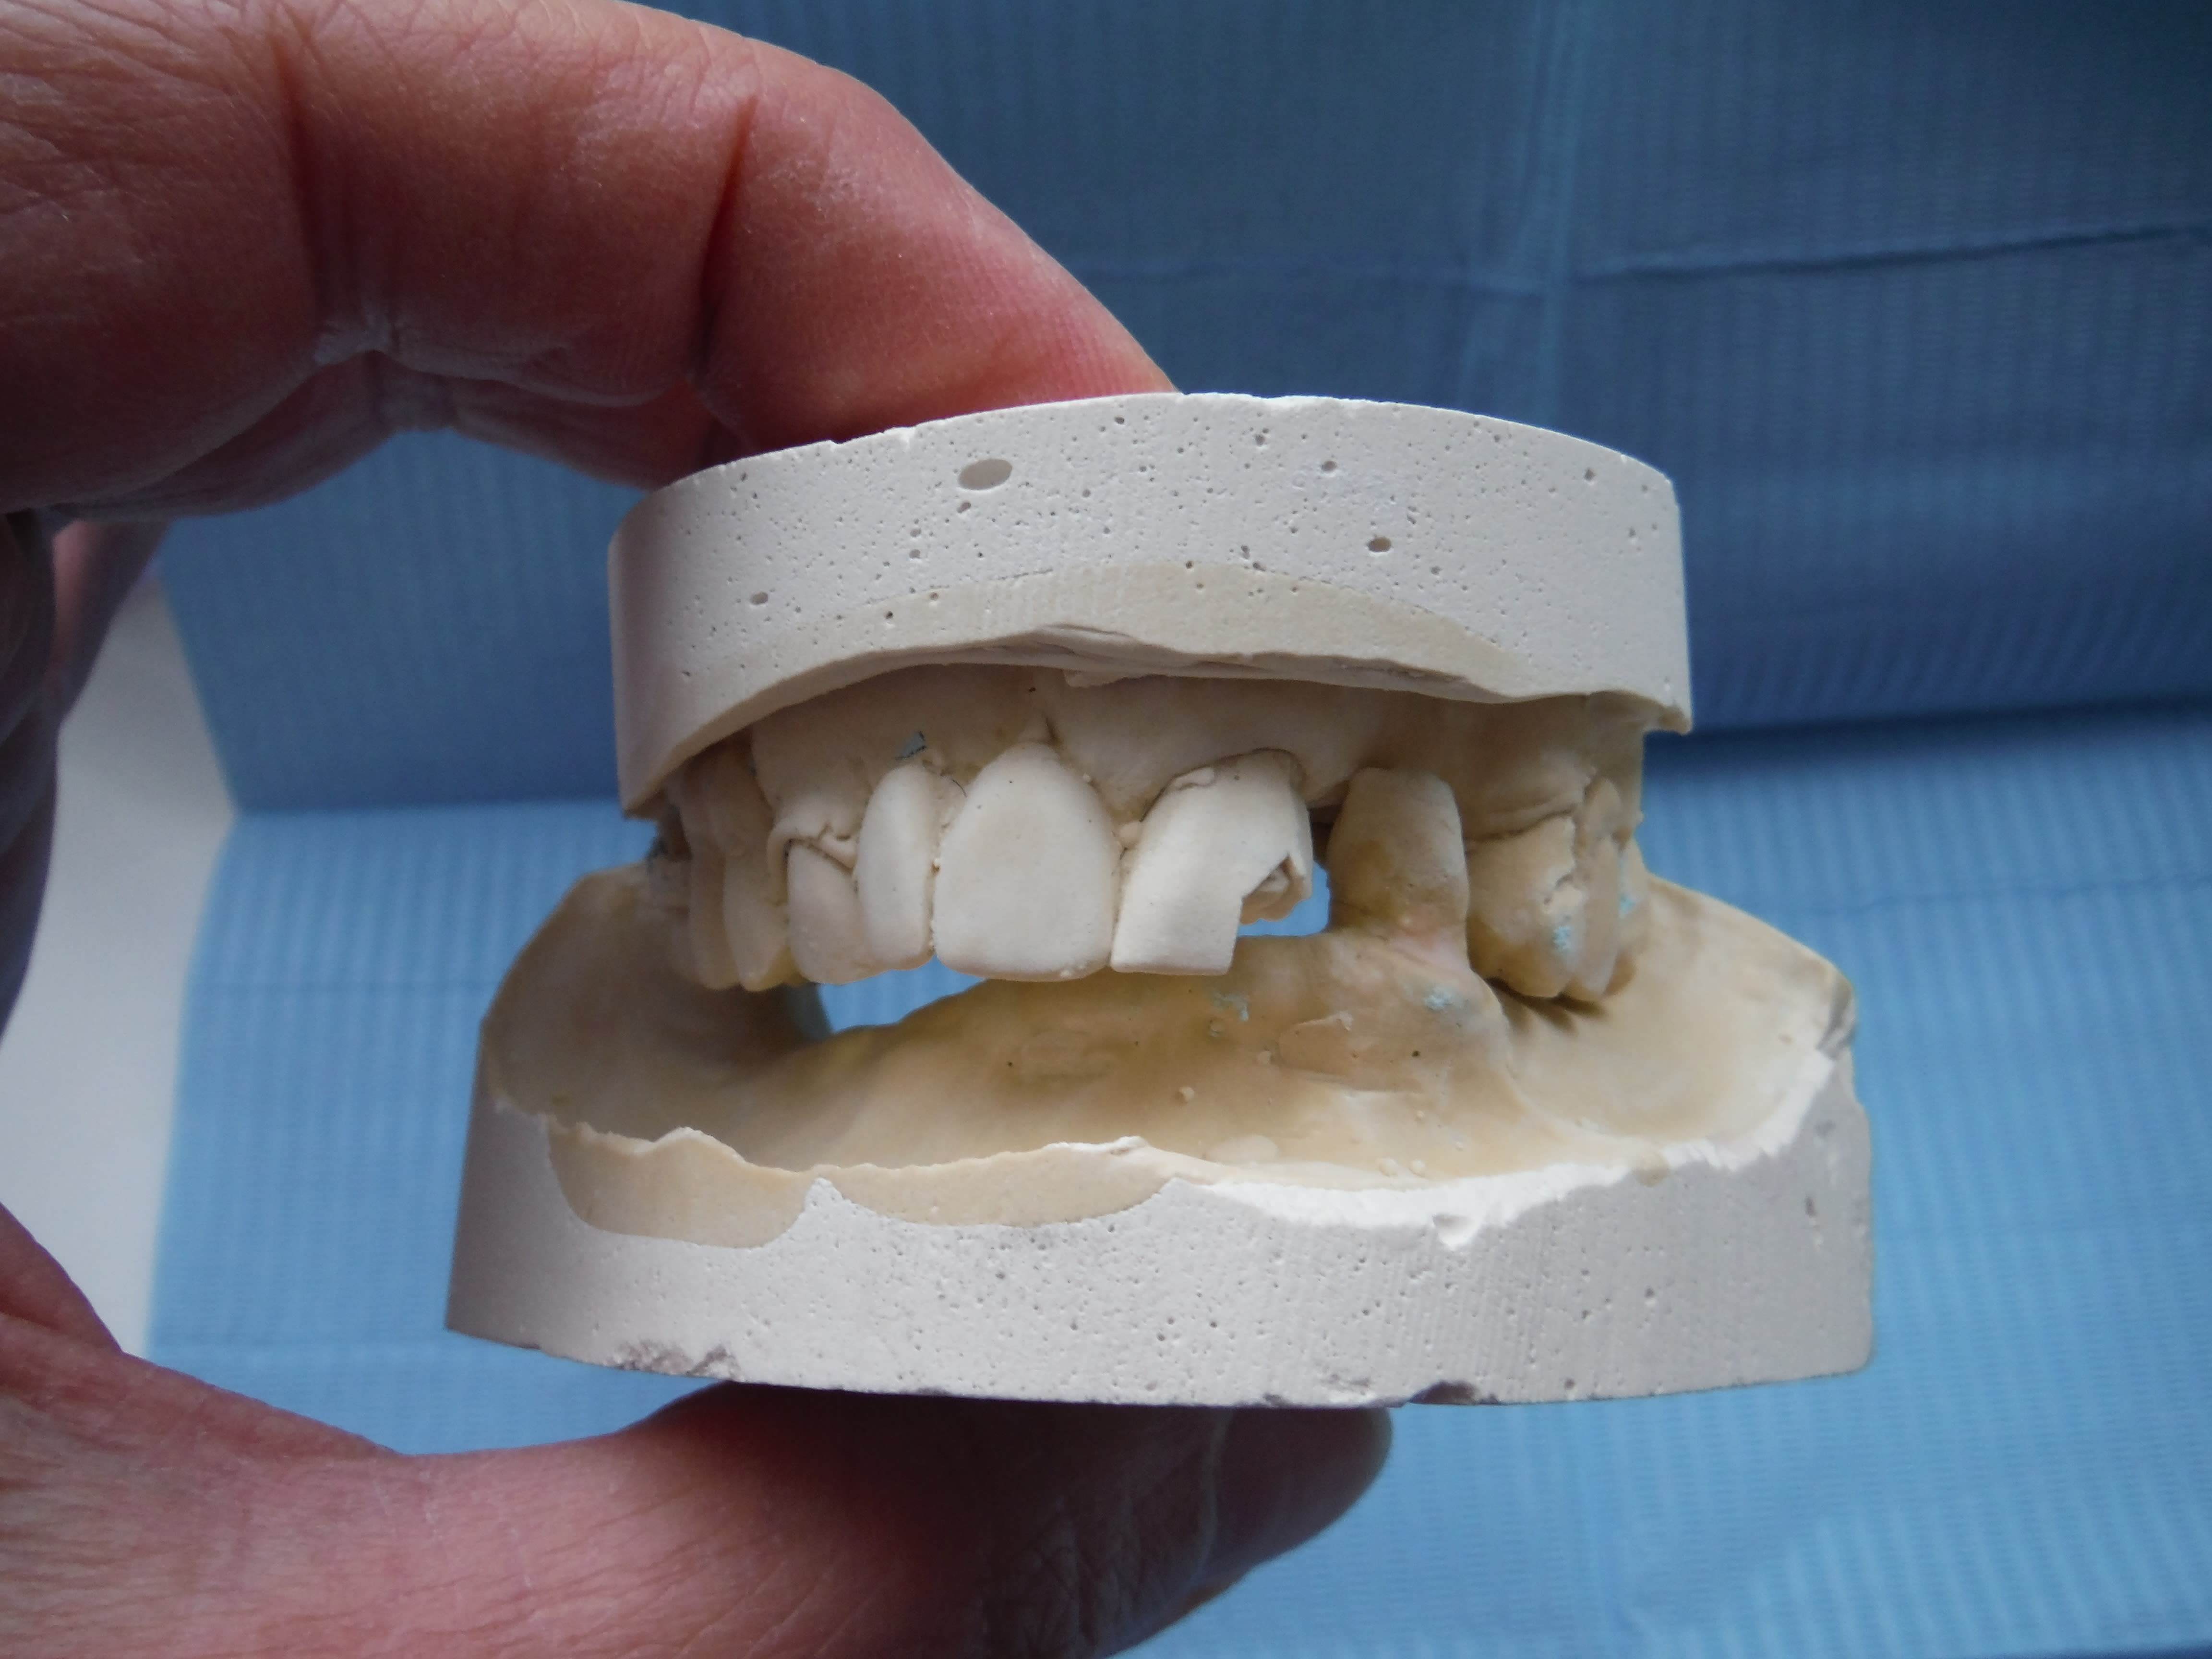

Et là tu vois quoi? Faut que j’adresse à un esssspécialiste?

Plus de 10 ans qu'il n'y a rien en bas, et là le coup de bol, elle s'est faite renverser par une voiture, avec les sous touchés elle va pouvoir se payer une pap/pac(?) C'est-y pas chouette?

La RC j't'en parle pas... trop simple!

Dscf3069 s3usgb - Eugenol

Dscf3070 saszen - Eugenol

Dscf3071 fpbucp - Eugenol

Je vois que tu vas en baver .:-)